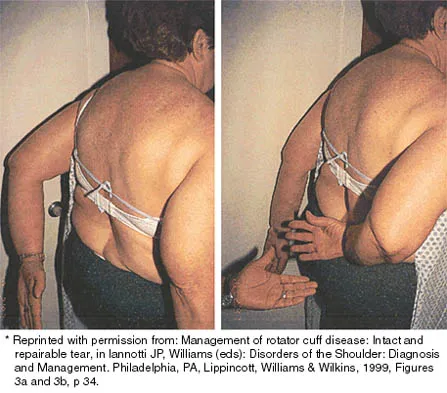

A 30-year-old man underwent an open Bankart repair with capsulorrhaphy for recurrent anterior instability 6 months ago. In a recent fall, he described a hyperabduction and external rotation mechanism of injury. He denies dislocating his shoulder. He now has anterior shoulder pain, weakness, and the sensation of instability. Examination reveals tenderness just lateral to the coracoid and bicipital groove. An MRI scan is shown in Figure 31. Management should now consist of

Explanation